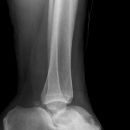

Talus Fraktur